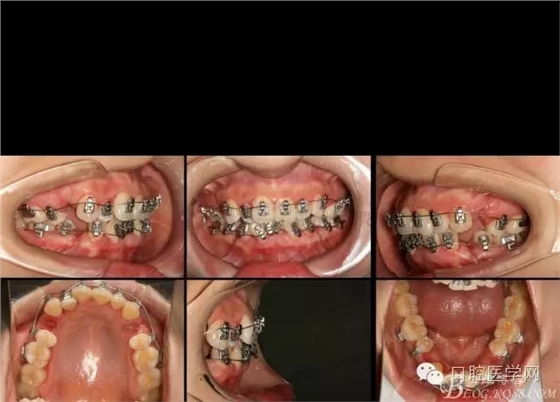

2016.3.3初裝矯正器,014Tn絲激活牙齒,利用交互支抗初步排齊前牙,為主弓絲置入創(chuàng)造更好條件。

2016.4.8 第一次復(fù)診,換為022*016tn扁絲,在上下尖牙遠中用等力拉簧滑動關(guān)閉,內(nèi)收前牙。